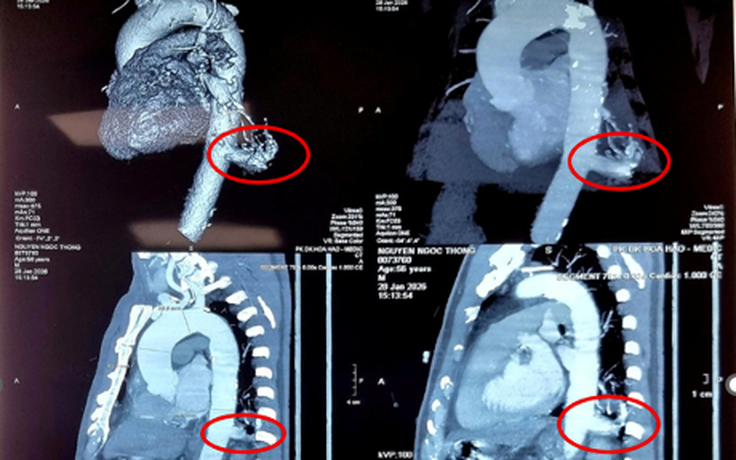

Bệnh viện Bình Dân vừa thực hiện thành công trường hợp phẫu thuật robot tạo hình cơ hoành trái, giúp bệnh nhân nhão hoành thoát khỏi tình trạng khó thở kéo dài. Đây là lần đầu tiên robot phẫu thuật được ứng dụng trong tạo hình cơ hoành cho người bệnh nhão hoành, giúp người bệnh ít tổn thương, ít đau, ít mất máu và xuất viện sớm.